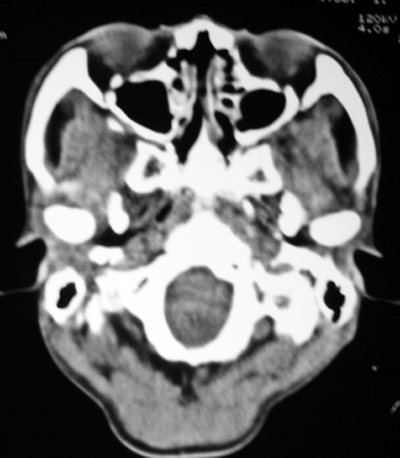

以下是引用随光逐影在2009-4-23 19:35:00的发言:[br]1)鼻咽、口咽、左侧鼻腔及右侧鼻后孔处新生物,考虑息肉可能性大。2)双侧上颌窦及双侧筛窦炎症,不排除双侧上颌窦内息肉可能。